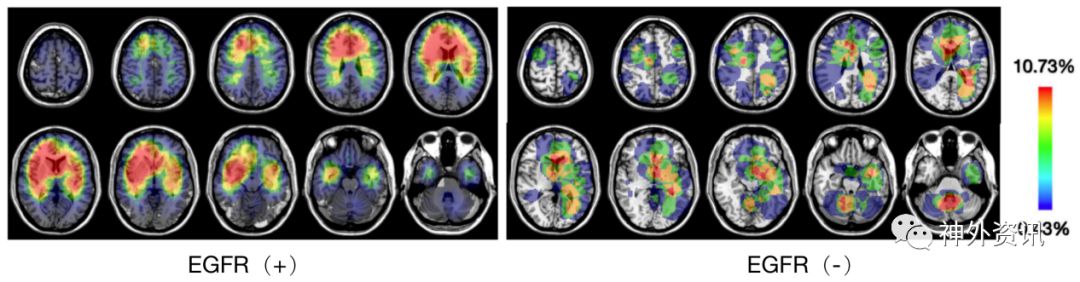

我院2012-2017年胶质母细胞瘤中,用免疫组化方法区分EGFR阳性与EGFR阴性的病例,在肿瘤位置分布上有明显的差别,分布在后颅凹第四脑室周围的胶质母细胞瘤,几乎均为EGFR免疫组化阴性(图8)

![]()

图8. EGFR免疫组化阳性与阴性胶质母细胞瘤的位置分布差异。红色体素表示肿瘤出现的频率高,蓝色体素标识肿瘤出现的频率低。(浙医二院未发表资料)